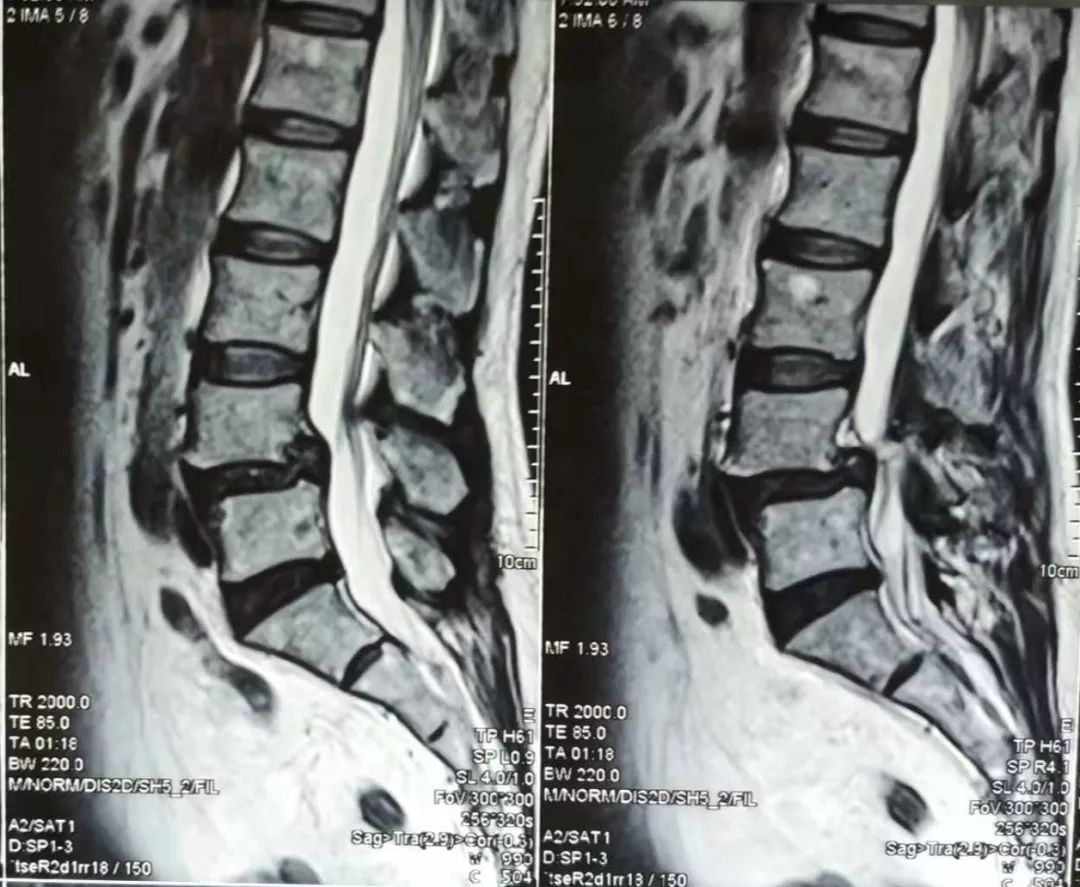

术前MRI

腰4椎体峡部不连续伴假关节形成, 增生退变,继发腰4椎体向前轻度滑脱

本病例中,患者腰4椎体II度滑脱,伴腰4-5椎间盘突出,相应水平椎管狭窄,手术指征明确。患者合并重度骨质疏松,故手术中使用骨水泥钉固定的同时在螺钉周围注射骨水泥增强螺钉把持力。